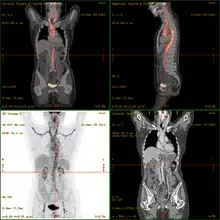

- 18F-fluorodeoxyglucose positron emission tomography/computed tomography (FDG-PET/CT)has become a widely used imaging tool in patients with suspected Large Vessel Vasculitis, due to the enhanced glucose metabolism of inflamed vessel walls.[11] The combined evaluation of the intensity and the extension of FDG vessel uptake at diagnosis can predict the clinical course of the disease, separating patients with favourable or complicated progress.[12]